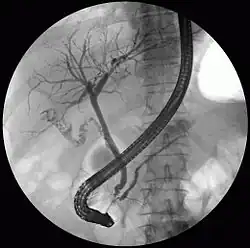

![]() ERCP image showing the biliary tree and the main pancreatic duct. | |